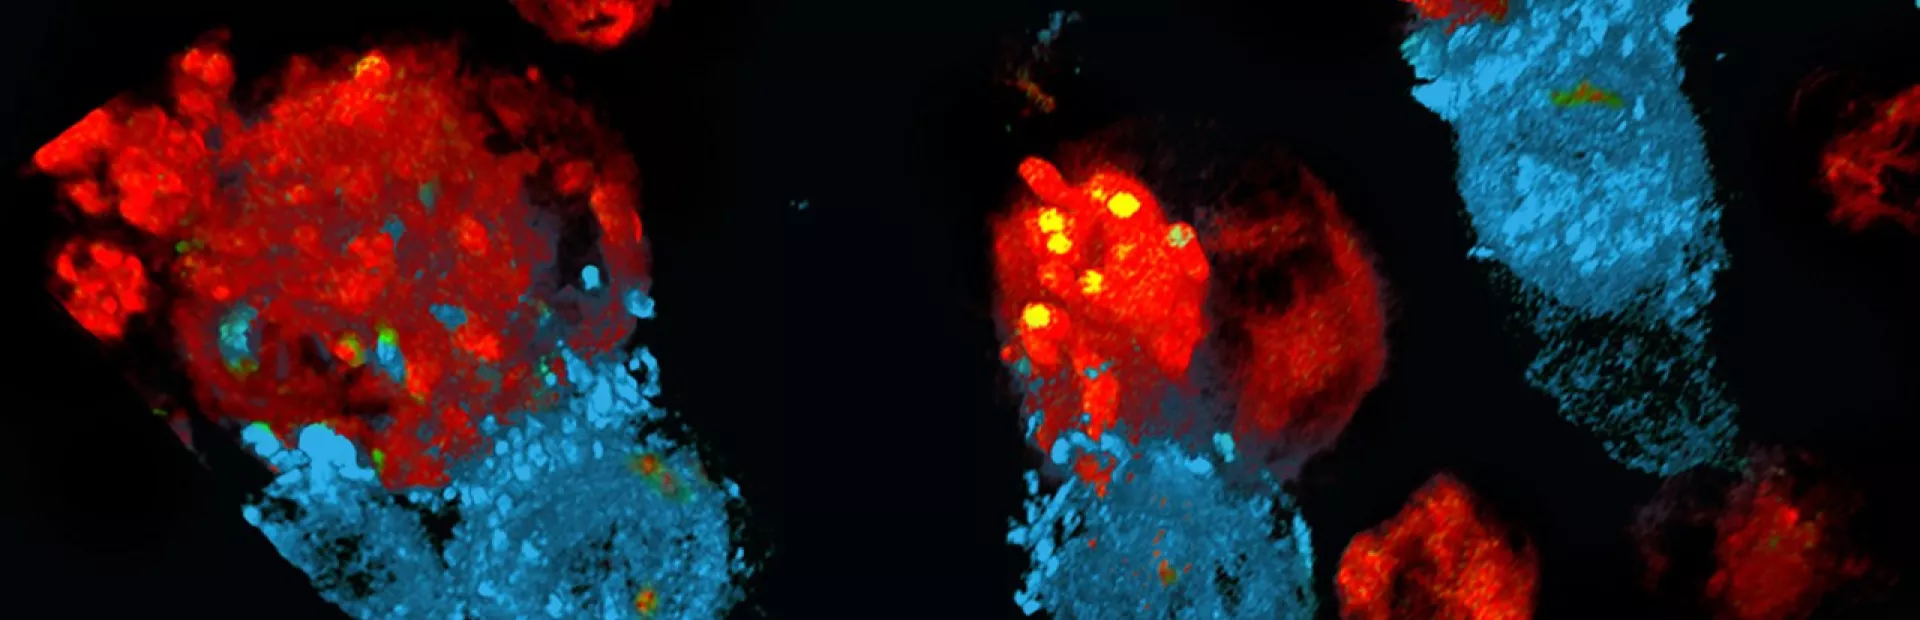

Celle- og genterapier bygger på grundig forskning, der bygger på mange årtiers videnskabelige fremskridt. De centrale redskaber og teknologier er blevet afprøvet og raffineret af utallige eksperter – først i laboratoriet og sidenhen i klinikken. Ved celleterapi dyrkes eller modificeres cellerne uden for kroppen, før de indsprøjtes i patienten, hvor de udvikler sig til et "levende lægemiddel". Ved genterapi udskiftes, inaktiveres eller indføres generne i celler – enten uden for eller inde i kroppen – for at behandle en sygdom. Nogle behandlinger kvalificerer sig som både celle- og genterapier.

Den enkelte celle- og genterapi udvikles på grundlag af detaljeret information om årsagerne til en patients sygdom. Den behandler en tilstand eller sygdom ved kilden ved på genniveau at reparere eller forbedre celler. Hos Novartis samarbejder vi inden for celle- og genterapi for at bringe denne revolutionerende behandlingsform til patienter med en lang række sygdomme, herunder genetiske sygdomme og visse livstruende kræftformer.